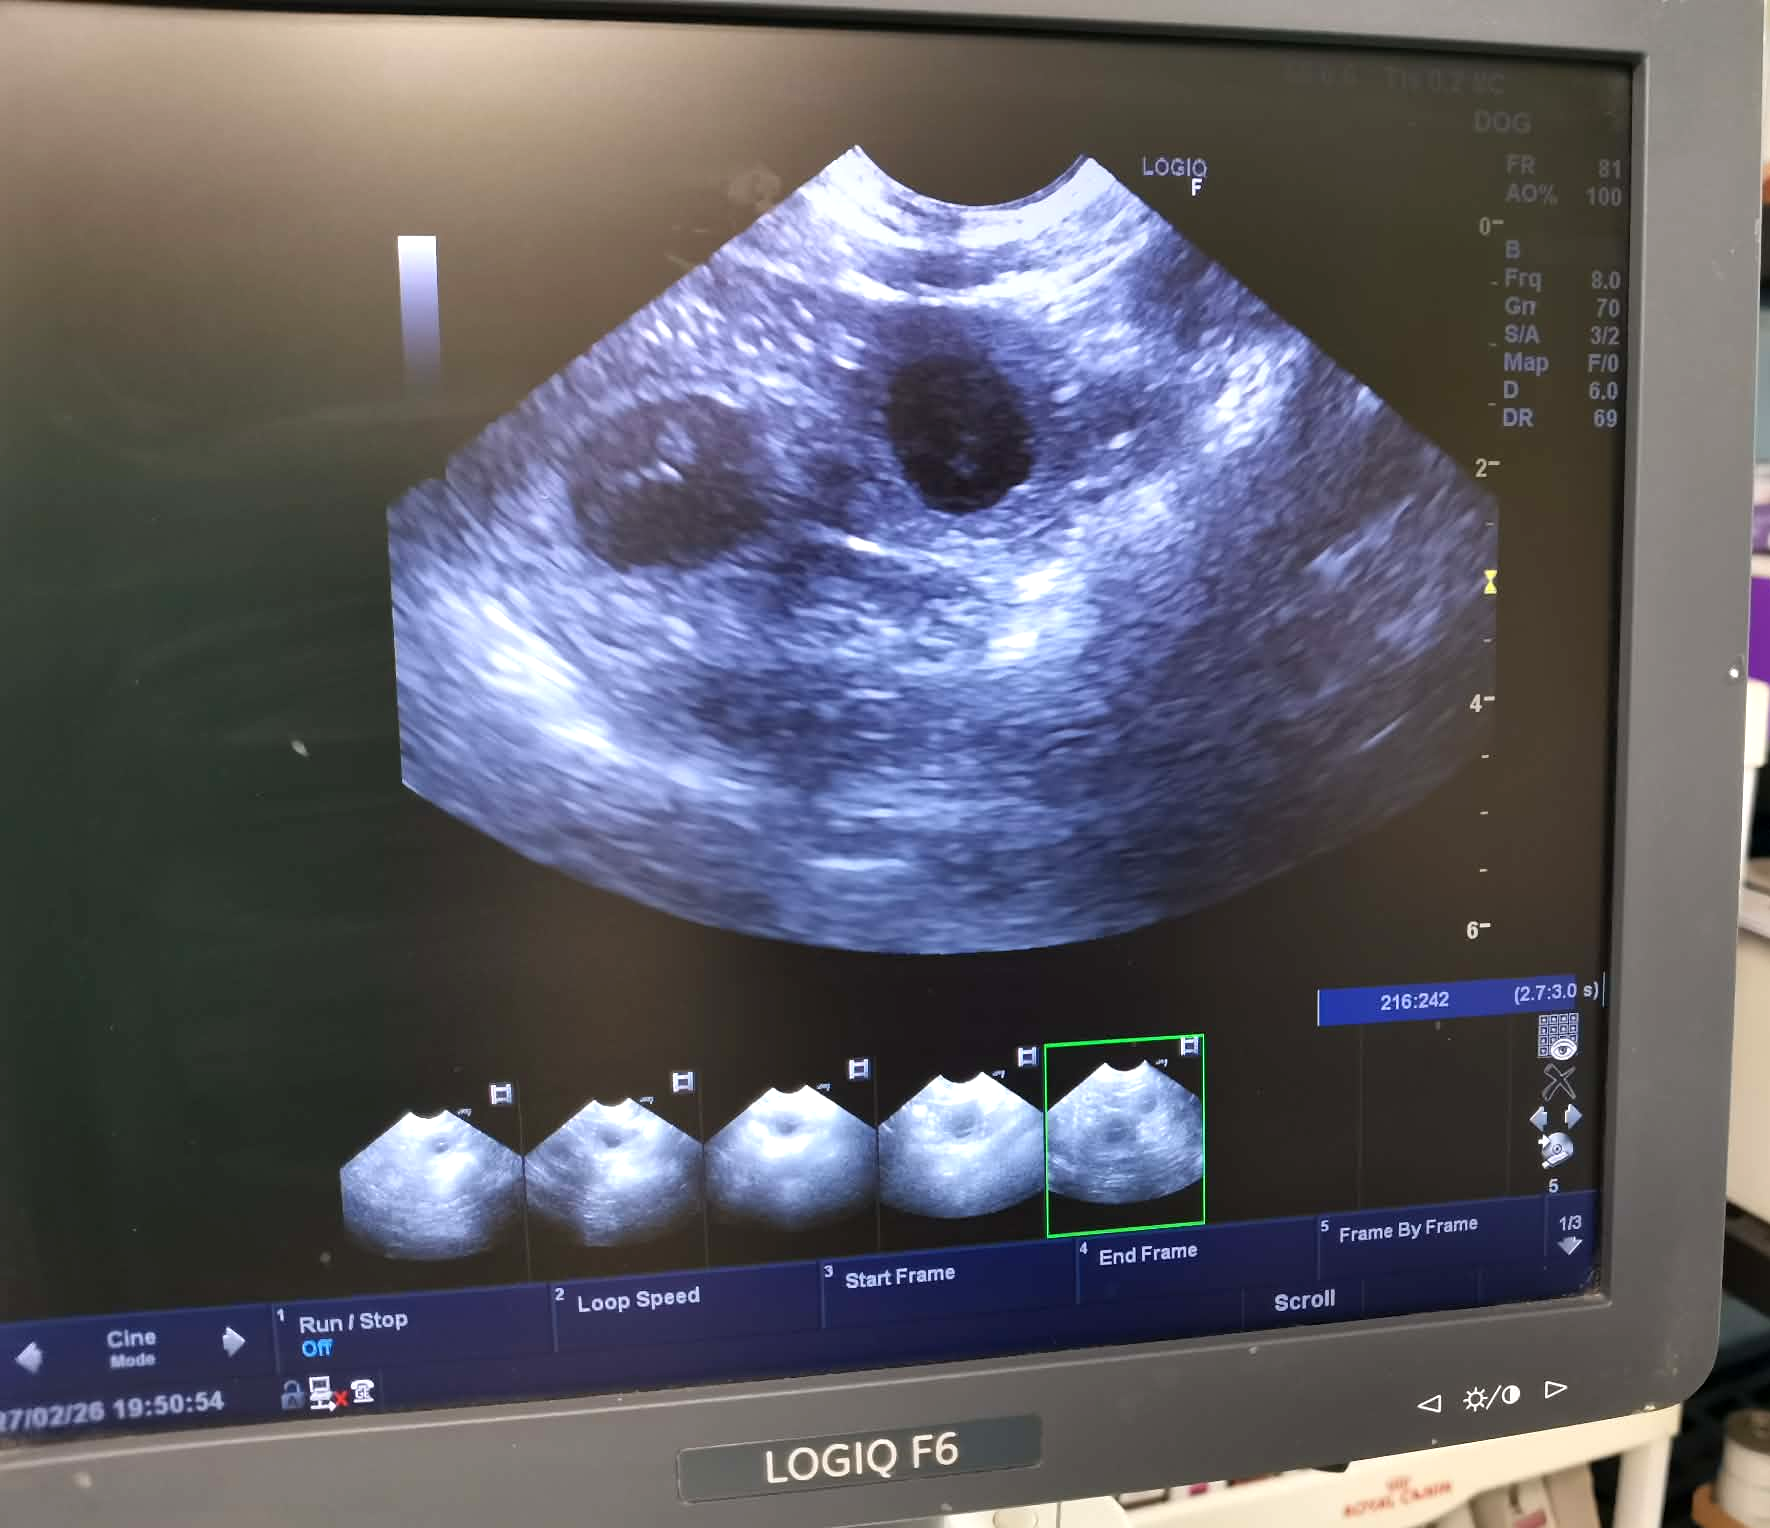

Špunti se narodili v úterý 7.4.2026 v noci císařským řezem - jedna merle fenečka a jeden triko pejsek. Před porodem jsme dělali rentgen a byla jasně vidět dvě štěňátka, případně jedno v zákrytu, ale ve výsledku byla opravdu jen dvě.